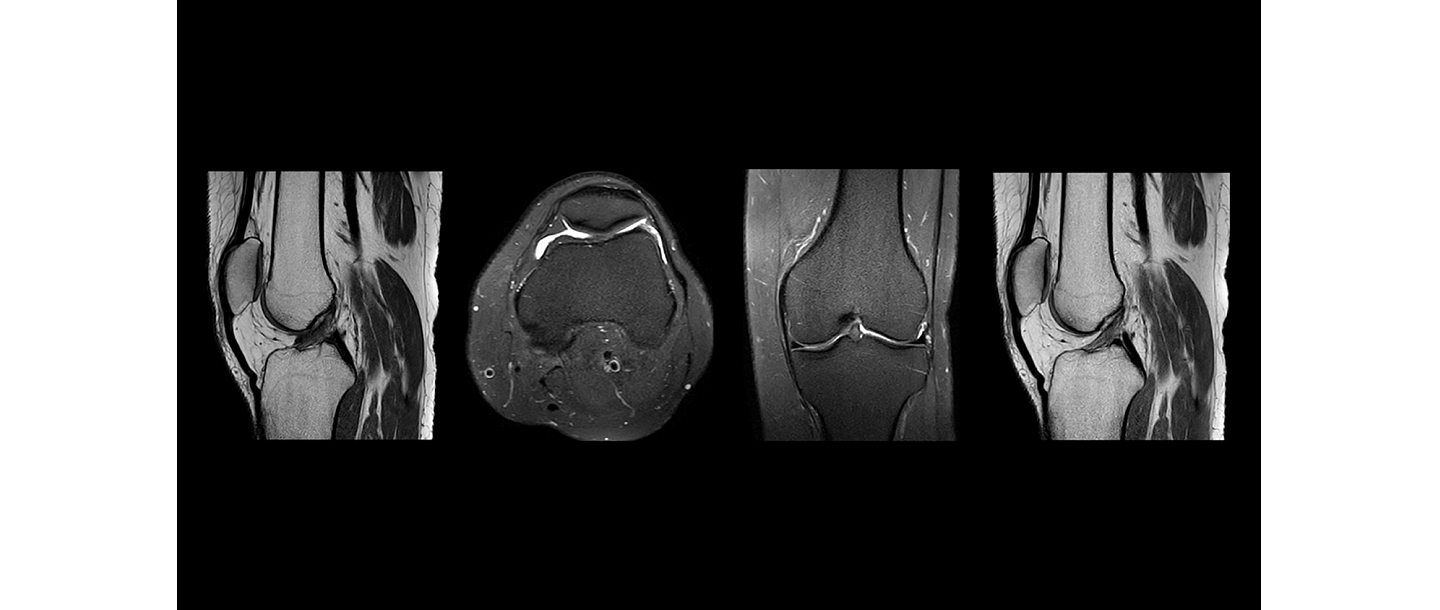

Magnētiskā rezonanse

MRI Teika